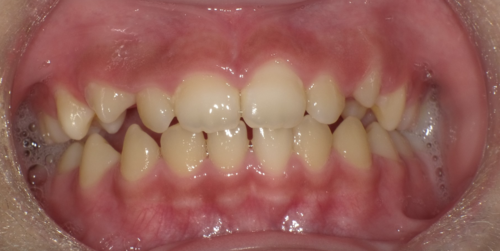

前歯が全体的に受け口になっている症例はもちろんですが、下の写真のように1本だけ反対になっている症例にも効果があります。

↓

4カ月で左前歯の反対咬合が改善されています。さらに歯列の拡大も見られます。